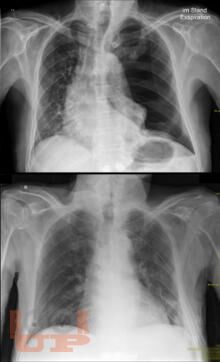

Спонтанный пневмоторакс

Ханнанов Н. И. Спонтанный пневмоторакс : учебное пособие для врачей / Н. И. Ханнанов, В. В. Фаттахов, М. Н. Насруллаев. - Казань : КГМА, 2020. - 40 c. - Текст : электронный // ЭБС "Букап" : [сайт]. - URL : https://www.books-up.ru/ru/book/spontannyj-pnevmotoraks-16035604/ (дата обращения: 11.11.2025). - Режим доступа : по подписке.